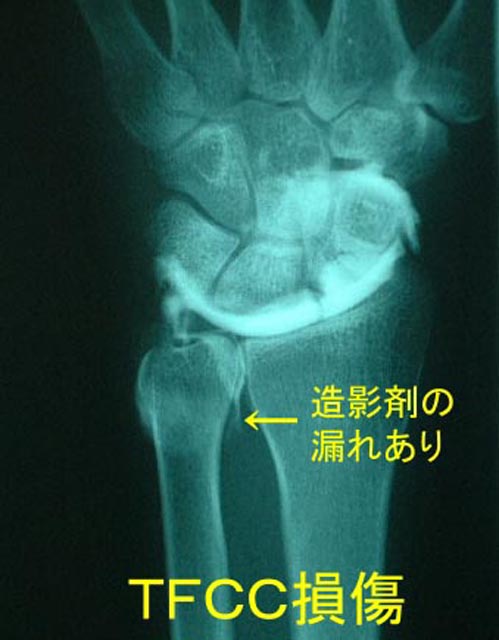

診察でTFCCストレステストが陽性となります(手関節を小指側に屈曲した状態で、手関節に対し軸圧を加えると痛がります)。また、バロットメントテスト陽性です(遠位の尺骨を上下に動かすと関節がグラグラする)。レントゲンでは特徴的な異常所見を認めません。時に、

尺骨の突き上げ(尺骨が橈骨に比べ上方に突出している状態)を認めることがあります。診断はMRI関節造影関節鏡などで確定されます。